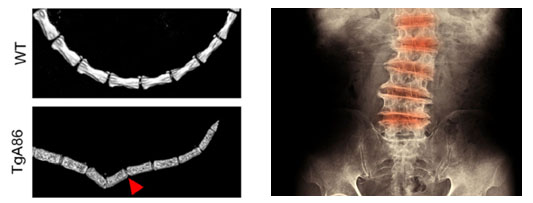

Newly published Biomedcode .... a novel transmembrane #TNF driven #mouse model of human #spondyloarthritis. A #translational tool for the study of #SpA pathogenesis and the evaluation of human #therapeutics. arthritis-research.biomedcentral.com/track/pdf/10.1…

.... a novel transmembrane #TNF driven #mouse model of human #spondyloarthritis.

A  #translational tool for the study of #SpA pathogenesis and the evaluation of human #therapeutics.

arthritis-research.biomedcentral.com/track/pdf/10.1…